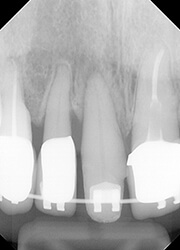

【治療前】

転倒してしまい、右上1(中切歯)の唇側がひどく腫れて来院されました。

写真では分かりにくいですが、右上の1番(中切歯)の唇側に骨に至るほどの破折が確認できました。

写真からは生活歯ですし、どうしようか悩みました。